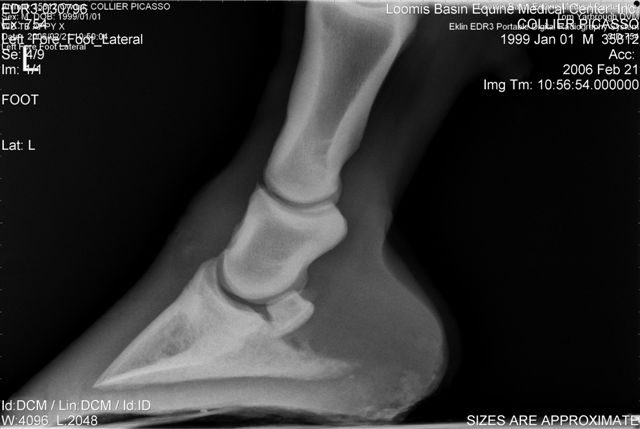

Let's label the radiographs from left to right with numbers. The abnormalities I see on the L using the photo's number as reference:

1) Odd lucency (darker) at the top/lateral margin of the coffin bone (seen in many images). It would interesting if this is also the site of the odd bruising.

2) Decrease lucency (darker) in the body of the navicular bone.

2) Remarkable cone shape areas of decrease lucency (darker) along the distal margin of the navicular bone.

3) Assymetrical flexor surface of the navicular bone.

4) There is the appearance of poor ap balance of the foot with the heels being low

4) Soles appear thin

4) Small osteophyte (bone spur) on the front margin of the pastern joint.

On the right the main problem is the appearance of the n. bone in the first image. It appears to have large irregular areas of increased lucency surrounding areas of decreased lucency. The darker areas (decreased lucency) may be artifacts or represent thinning of cortical bone.

Unless there is something I am missing in the images the extensor process appears to have healed well on the L. The significance of each of these lesions will depend on clinical findings Ann and confirmation that these are actual lesions and not artifacts created by positioning or the foot preparation for radiography. You should note I am not a radiologist and that viewing images in this manner is not as revealing as viewing the radiographs first hand.